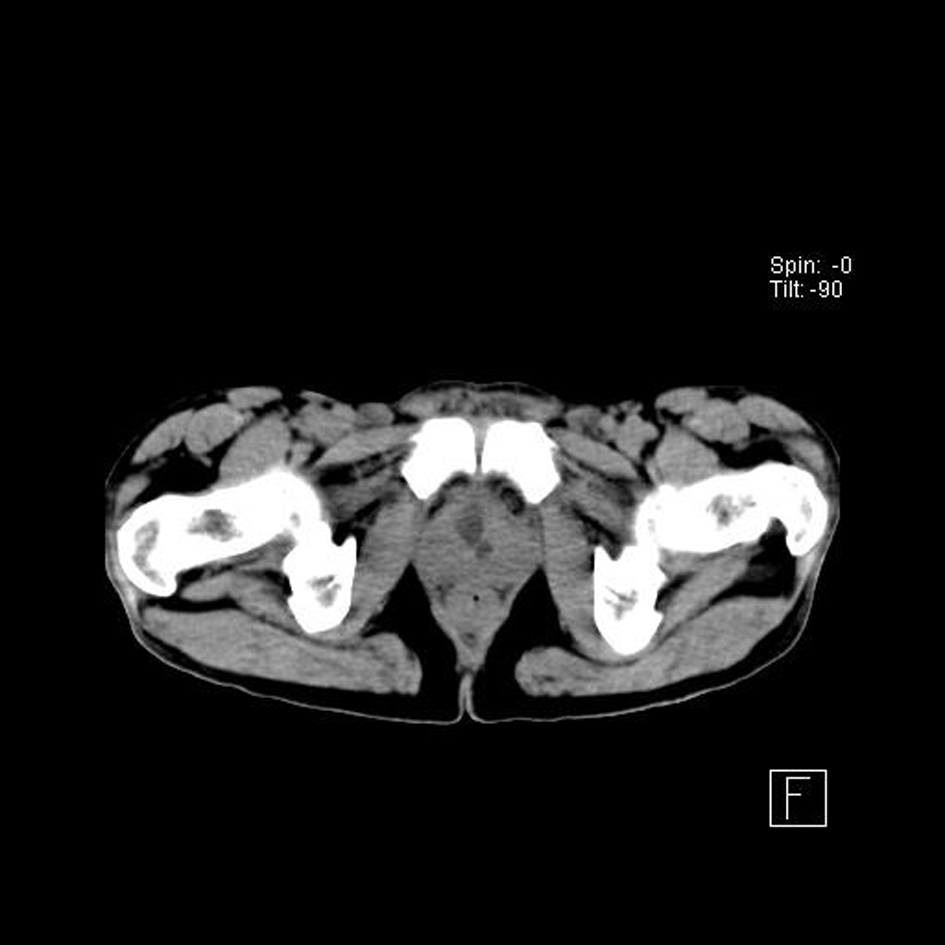

Ultrasonograph of abdomen revealed bilateral hydroureteronephrosis with hardly any parenchyma on left side with ectopic opening of ureters in the proximal prostatic urethra. TRUS examination showed non-visualized left seminal vesicle in addition to the above findings. Non-contrast CT (Fig. 1-3) and MRI showed the anatomical details but no ureterocele was reported. No vesicoureteric reflux was seen in the voiding cystourethrogram film.

![]() Click for large image | Figure 3. Ureters opening into proximal prostatic urethra. |